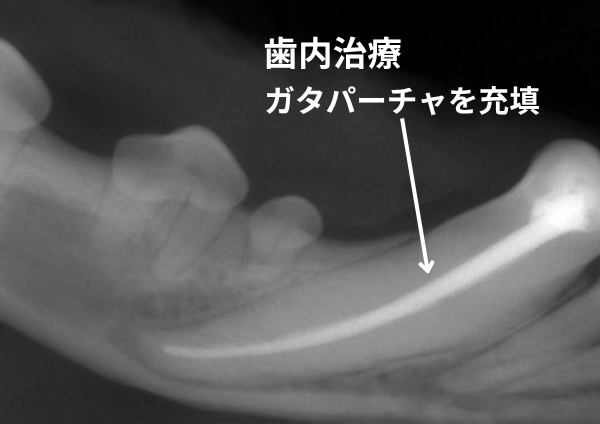

4歳のMIX犬が、5日前に歯が折れていることに気づき、来院しました。玄関の段差に顔をぶつけたとのことでした。下顎の犬歯が複雑破折して、露髄していたため、歯を温存する歯内治療を行いました。歯髄の充填は、ガタパーチャとMTAシーラーを用いて行いました。

下顎犬歯の抜歯は難易度が高く、様子見と言われてしまうこともありますが、露髄していると、そこから必ず感染が起こります。歯内治療では歯髄を除去し、ゴム製剤を充填することにより、歯を残しながらも感染を防ぐことができます。